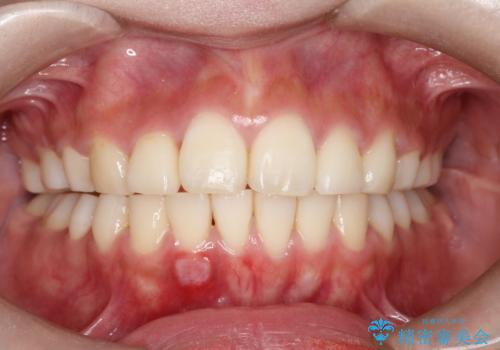

マウスピース矯正中のクリーニング pmtc

担当医 歯科衛生士